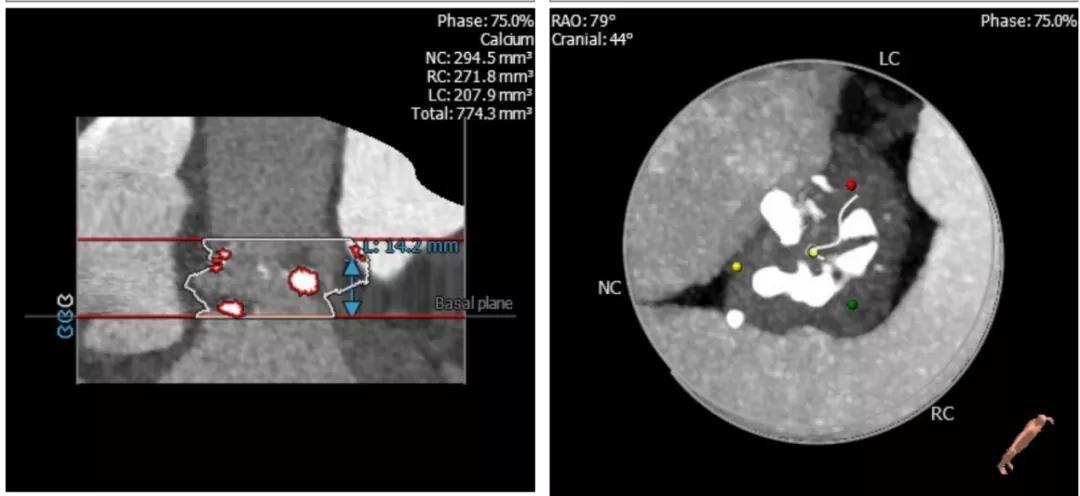

这个病人从超声看,是一个以反流为主的病例,狭窄只是中度,左室已经70。从CT分析看,瓣环-流出道呈开放性,左右冠瓣可疑融合,左冠高度虽然有14,但是左冠瓣叶很长,增厚,提示有冠脉风险。导丝刚跨瓣,病人就出现室颤,经药物调整后暂时稳定,25的球囊预扩后发现左冠完全不显影,而且患者再次反复室颤,此时为了稳定循环,第二因为冠脉风险,决定先从左侧股动静脉上ECMO保护。

根部解剖: